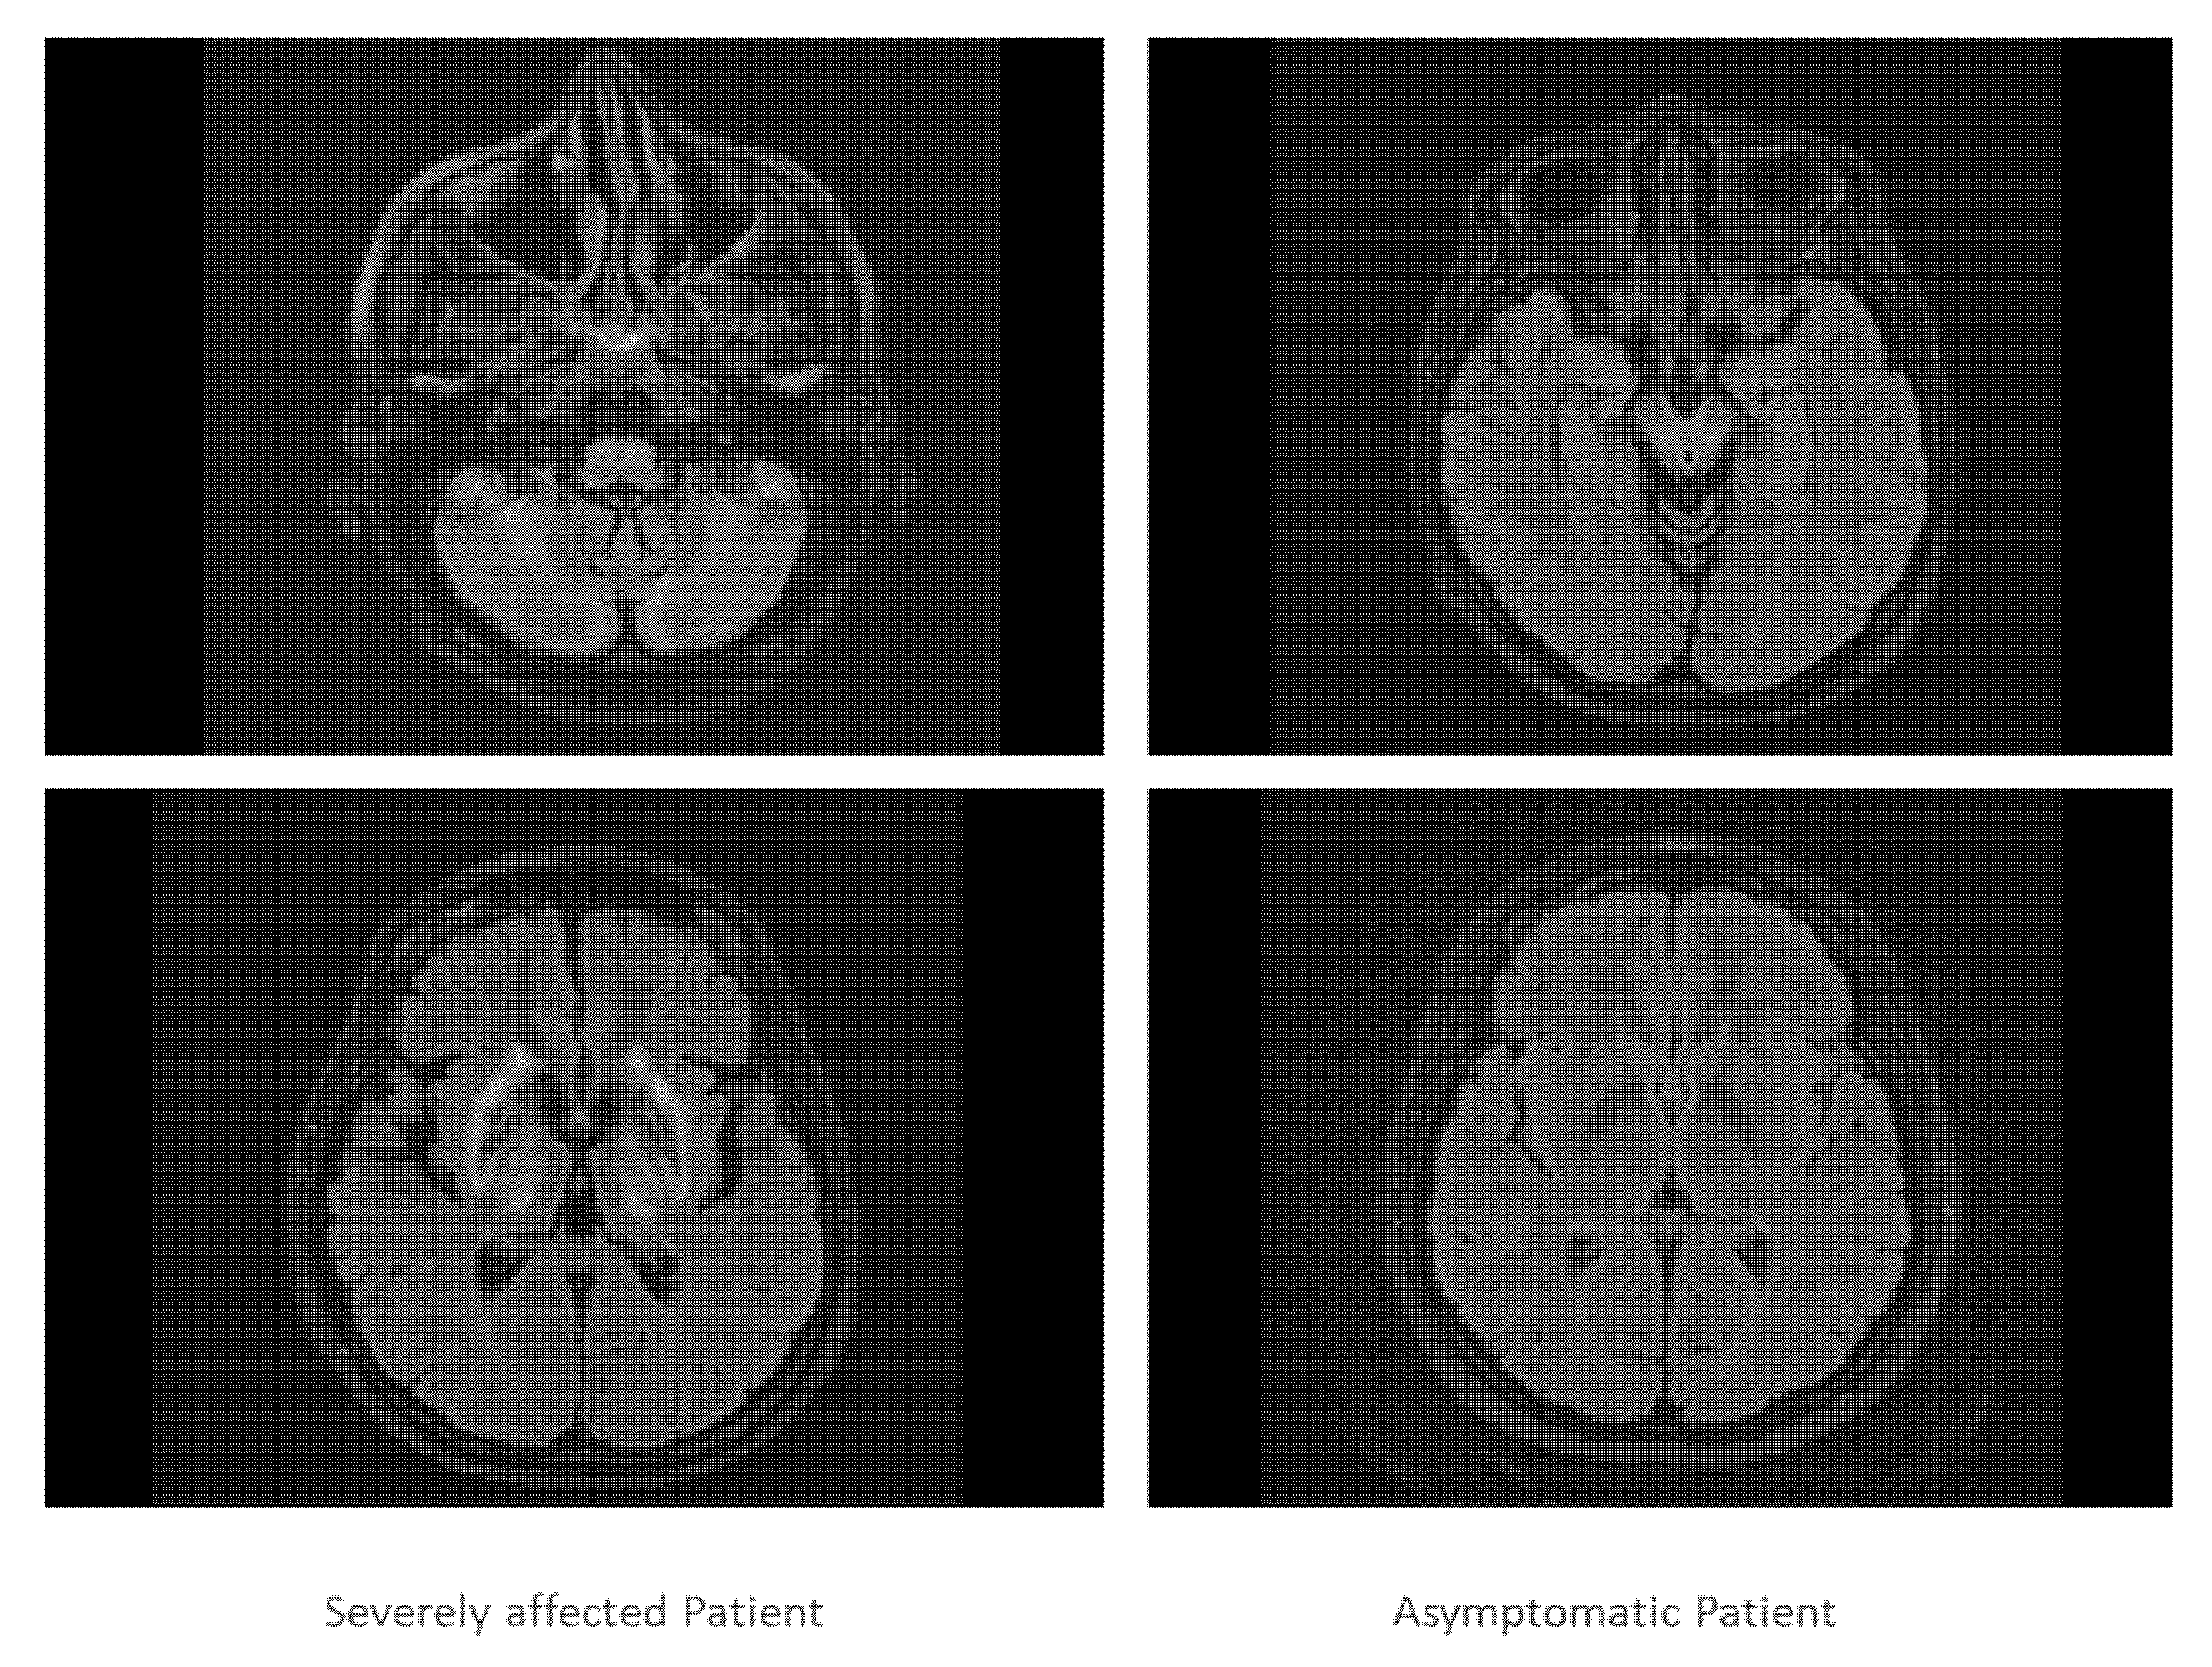

| cMRI | wide-spread impairment (comp. Figure 3 left side) | normal (Figure 3 right side) |

| MRI | hyperintensive areas on T2- weighted images in the BG cortical and subcortical brain atrophy | normal |

| cMRI | increased signal in T2-weighted images of BG, thalamus, mesencephalon, pons and cerebral peduncle, distinct atrophy of cerebellum and features of brainstem atrophy | increased signal in T2-weighted images of the lenticular ganglia, thalamus, cerebral peduncle and pons |